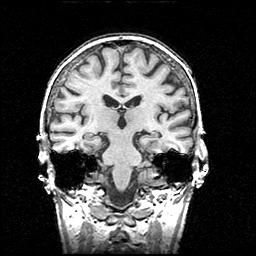

MR Study #1 -- Slice #58

[Home][Help][Clinical] Slice 58